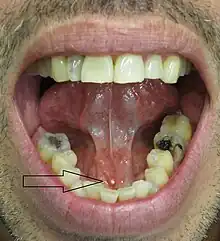

Salivary stones may be divided according to which gland they form in. About 85% of stones occur in the submandibular gland,[3] and 5–10% occur in the parotid gland.[2] In about 0–5% of cases, the sublingual gland or a minor salivary gland is affected.[2] When minor glands are rarely involved, caliculi are more likely in the minor glands of the buccal mucosa and the maxillary labial mucosa.[4] Submandibular stones are further classified as anterior or posterior in relation to an imaginary transverse line drawn between the mandibular first molar teeth. Stones may be radiopaque, i.e. they will show up on conventional radiographs, or radiolucent, where they not be visible on radiographs (although some of their effects on the gland may still be visible). They may also symptomatic or asymptomatic, according to whether they cause any problems or not.

- Palpable hard lump, if the stone is located near the end of the duct.[1][3] If the stone is near the submandibular duct orifice, the lump may be felt under the tongue.

- Erythema (redness) of the floor of the mouth (infection).[3]

- Pus discharging from the duct (infection).[3]